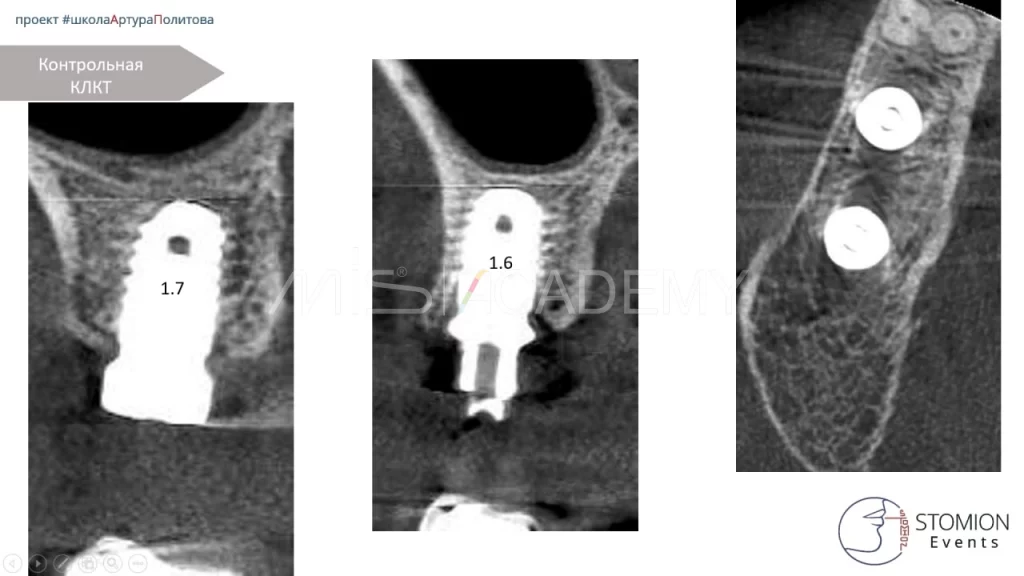

— Через 4 месяца на контрольном КЛКТ выявлены признаки резорбции костной ткани вокруг вновь установленного имплантата.

— Повторный анализ ситуации выявил истинную причину: хронический периодонтит зуба 1.6, который привел к резорбции тканей и поломке предыдущего имплантата.